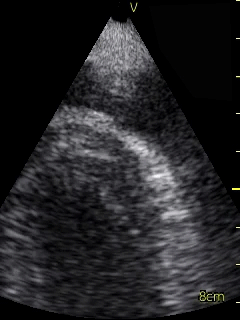

Video 1 (online supplement; Figure 1) demonstrates a parasternal long axis view with the pericardial effusion noted to be posterior to the left ventricle in this view. Video 2 (online supplement; Figure 2) is a short axis view of the heart which is showing that the effusion is surrounding the heart. Video 3 and 4 (online supplements; Figures 3 & 4) demonstrates that the pericardial effusion is present significantly surrounding the apex as well. An echocardiogram confirmed the POCUS findings and cardiology was consulted to conduct a pericardiocentesis, following which the patient’s symptoms resolved. The effusion was thought to be chronic and transudative. In this case, the use of POCUS at the bedside allowed for rapid detection of a large pericardial effusion and subsequent treatment.